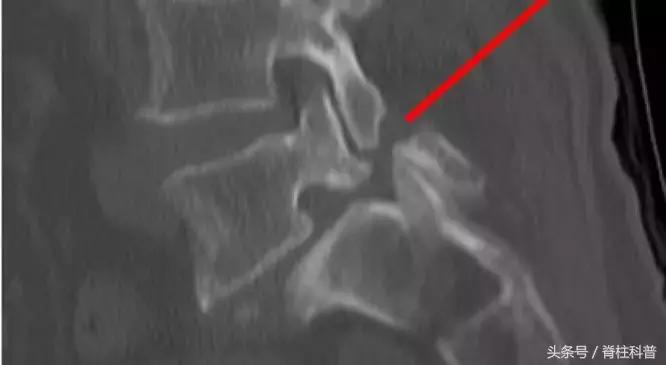

峡部裂